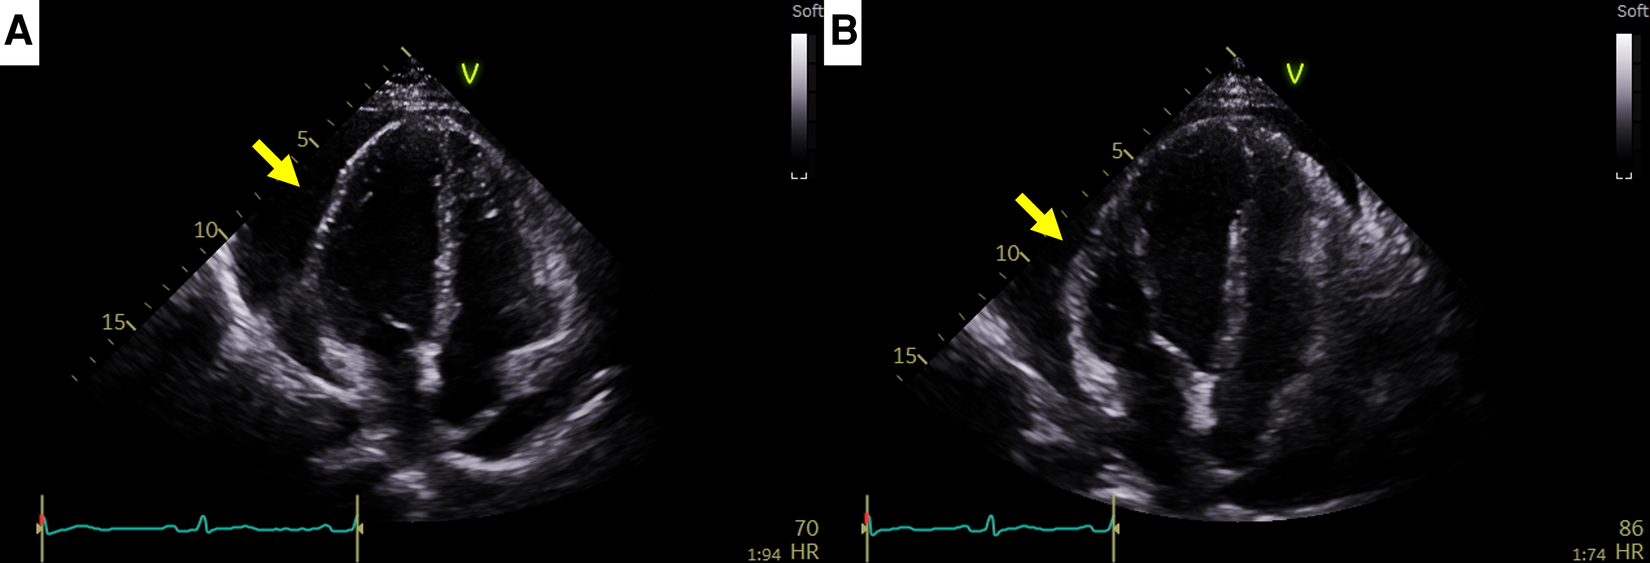

A 44-year-old female patient who had been undergoing 65 cycles of palliative chemotherapy with trastuzumab and pertuzumab for human epidermal growth factor receptor 2 (HER2)-positive MBC presented to the emergency department with dyspnea. The patient's blood pressure was 101/69 mmHg, and her pulse rate was slightly high at 105 beats per min (BPM). Initial electrocardiography (ECG) revealed a low-voltage QRS complex (Figure 1A), and her N-terminal pro-brain natriuretic peptide (NT-proBNP) level was relatively low (424 pg/ml). Therefore, we suspected cardiac tamponade and promptly performed echocardiography. A large PE with definite tamponade physiology was observed (Figure 1B, Supplementary Video 1), and emergent pericardiocentesis was performed. The next day, the ECG revealed a newly developed anterior T wave inversion (Figure 1C). Follow-up echocardiography showed markedly reduced PE, disseminated pericardial adhesions, and thickening with CP, suggesting effusive-constrictive pericarditis (ECP) (Figures 1D–F, Supplementary Video 2). Two days after pericardiocentesis, her dyspnea and tachycardia did not fully resolve, and the NT-proBNP level was elevated to 1,680 pg/ml, all of which were compatible with ECP. AIT against ECP was initiated using with prednisolone (started with 0.5 mg/kg/day, gradually tapered for 2 months) and colchicine (0.6 mg/day). A metastatic adenocarcinoma was identified on cytopathology in the drained PE, whereas no other possible causes of PE were identified in either serologic or PE analyses. Owing to the positive result of pericardial fluid cytopathology, we judged her breast cancer as a progressive disease and decided to change the cancer therapy to trastuzumab emtansine (T-DM1). However, cardiac tamponade recurred twice (2 and 5 months after initial pericardiocentesis, respectively), even after switching to T-DM1 (Figures 2A,B, Supplementary Videos 3 and 4), while other metastatic sites remained stable. Repeated pericardiocentesis and AIT for ECP were performed for each episode of cardiac tamponade. Despite recurrent cardiac tamponade episodes with T-DM1 therapy, we continued T-DM1 therapy with AIT because the symptoms and signs of heart failure were well controlled after pericardiocentesis and AIT. Furthermore, the oncological response to T-DM1 was thought to be stable, except for recurrent PE. Finally, after three times of pericardiocenteses, AIT, and eight cycles of T-DM1 therapy, cardiac tamponade has not recurred until now. The patient has been on T-DM1 maintenance therapy with an oncologic state of stable disease for two years.

Figure 2

Recurrent cardiac tamponade episodes in case 1. (A) Second cardiac tamponade episode with large pericardial effusion (arrow). (B) Third cardiac tamponade episode with large pericardial effusion (arrow).